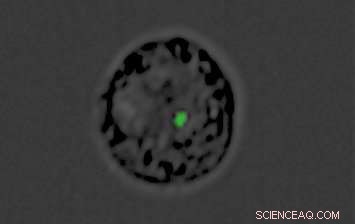

A monocyte converted into a decoy by the malaria parasite: The green dot is the genetic material "cargo" inside the nanovesicle produced by the parasite. Credit: Weizmann Institute of Science

In the new study, performed in collaboration with Prof. Andrew G. Bowie of Trinity College Dublin and other researchers, Regev-Rudzki and her Weizmann team discovered that in parallel with communicating with other parasites, Plasmodium falciparum uses this same communication channel for yet another purpose: to deliver a misleading message to the infected person's immune system. Within the first 12 hours after infecting red blood cells, the parasites send out DNA-filled nanovesicles that penetrate cells called monocytes. Normally, monocytes form the immune system's first line of defense against foreign invasion, sensing danger from afar and alerting other immune mechanisms to mount an effective response. Naturally, the immune system dispatches its next line of defense to these cells.

But in fact, the nanovesicles have converted the monocytes into decoys. While the immune system is busy defending the organism against fake danger, the real infection proceeds inside red blood cells, allowing the parasite to multiply unhindered at dizzying speed. By the time the immune system discovers its mistake, precious time has been lost, and the infection is much more difficult to contain.